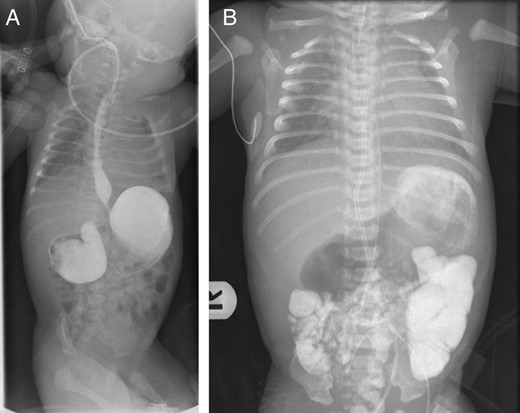

(A) Upper gastrointestinal contrast study showing a markedly distended stomach and duodenal bulb, with narrowed second part of duodenum suggesting congenital duodenal obstruction. (B) Delayed film of upper gastrointestinal contrast study showing dye passing distally suggestive of incomplete obstruction